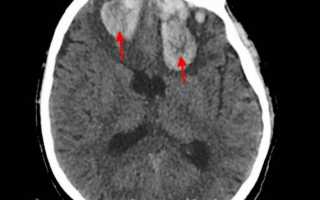

image

КТ головного мозга. Внутримозговые (интрапаренхиматозные) травматические гематомы с обеих сторон